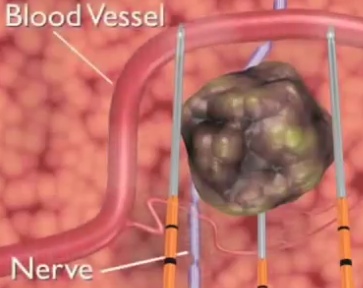

Opening the blood-brain barrier allows the body to remove plaque in the hippocampus